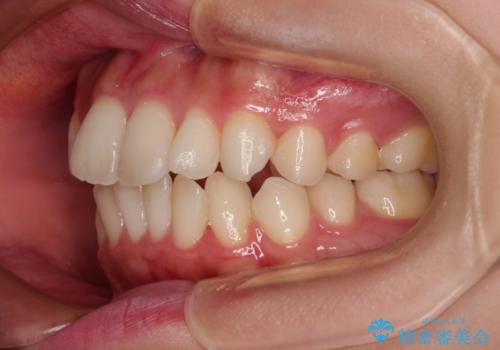

- 審美装置

- 1年10ヶ月

- 口元の突出感と口の閉じにくさを気にして来院された患者様です。

上下左右第一小臼歯4本を抜歯し、ワイヤー装置にて口元を引っ込めるよう矯正治療を行うこととしました。

口元の突出感が改善されてことで、下唇に引っかかっていた上顎前歯も気にならなくなりました。